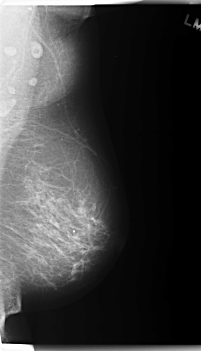

C_0179_1.RIGHT_MLO

LEFT_MLO LINES 5960 PIXELS_PER_LINE 3416 BITS_PER_PIXEL 12 RESOLUTION 50 NON_OVERLAY